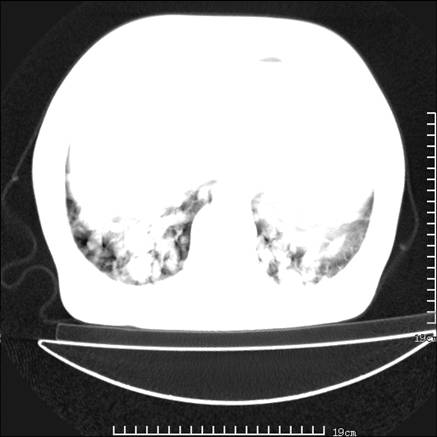

张男,75岁,干咳半年余,小便不利二年,b超检查前列腺增大,未见明显肿块;前列腺癌血生化检查多项指标明显增高。

双肺内多发转移瘤,纵膈淋巴结转移。来源前列腺?建议盆腔mri进一步检查。

双肺转移满了。

两肺广泛转移瘤。